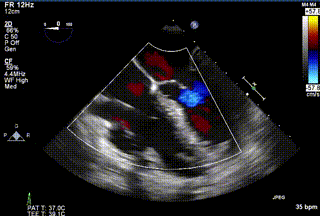

2021年12月24日,復(fù)旦大學(xué)附屬中山醫(yī)院葛均波院士團(tuán)隊成功應(yīng)用LuX-Valve Plus為一例極重度三尖瓣反流(TR)合并房顫、房缺的患者完成了經(jīng)血管三尖瓣置換術(shù),這是在前基礎(chǔ)上,本周完成的第三例經(jīng)血管三尖瓣置換手術(shù),葛均波院士、周達(dá)新教授等與心外科魏來教授、賴顥教授,心超室的潘翠珍教授、李偉教授及麻醉科的郭克芳教授共同完成了本周手術(shù),均獲得圓滿成功!患者術(shù)后超聲顯示無TR,臨床癥狀明顯改善。本周手術(shù)的成功也為LuX-Valve Plus救治性臨床研究添上了濃墨重彩的一筆。

三例患者入院后,葛均波院士團(tuán)隊周達(dá)新教授、潘文志教授、張源博士、陳莎莎博士及心超室的潘翠珍教授、李偉教授對患者的情況進(jìn)行詳細(xì)評估和討論,最終決定為三例患者選擇LuX-Valve Plus40mm、50mm和50mm型號的瓣膜進(jìn)行手術(shù)治療。手術(shù)后即刻拔除氣管插管,術(shù)后患者三尖瓣反流癥狀得到顯著改善,復(fù)查心超結(jié)果顯示人工三尖瓣瓣膜支架固定穩(wěn)定,瓣葉關(guān)閉形態(tài)未見異常,未見明顯反流。